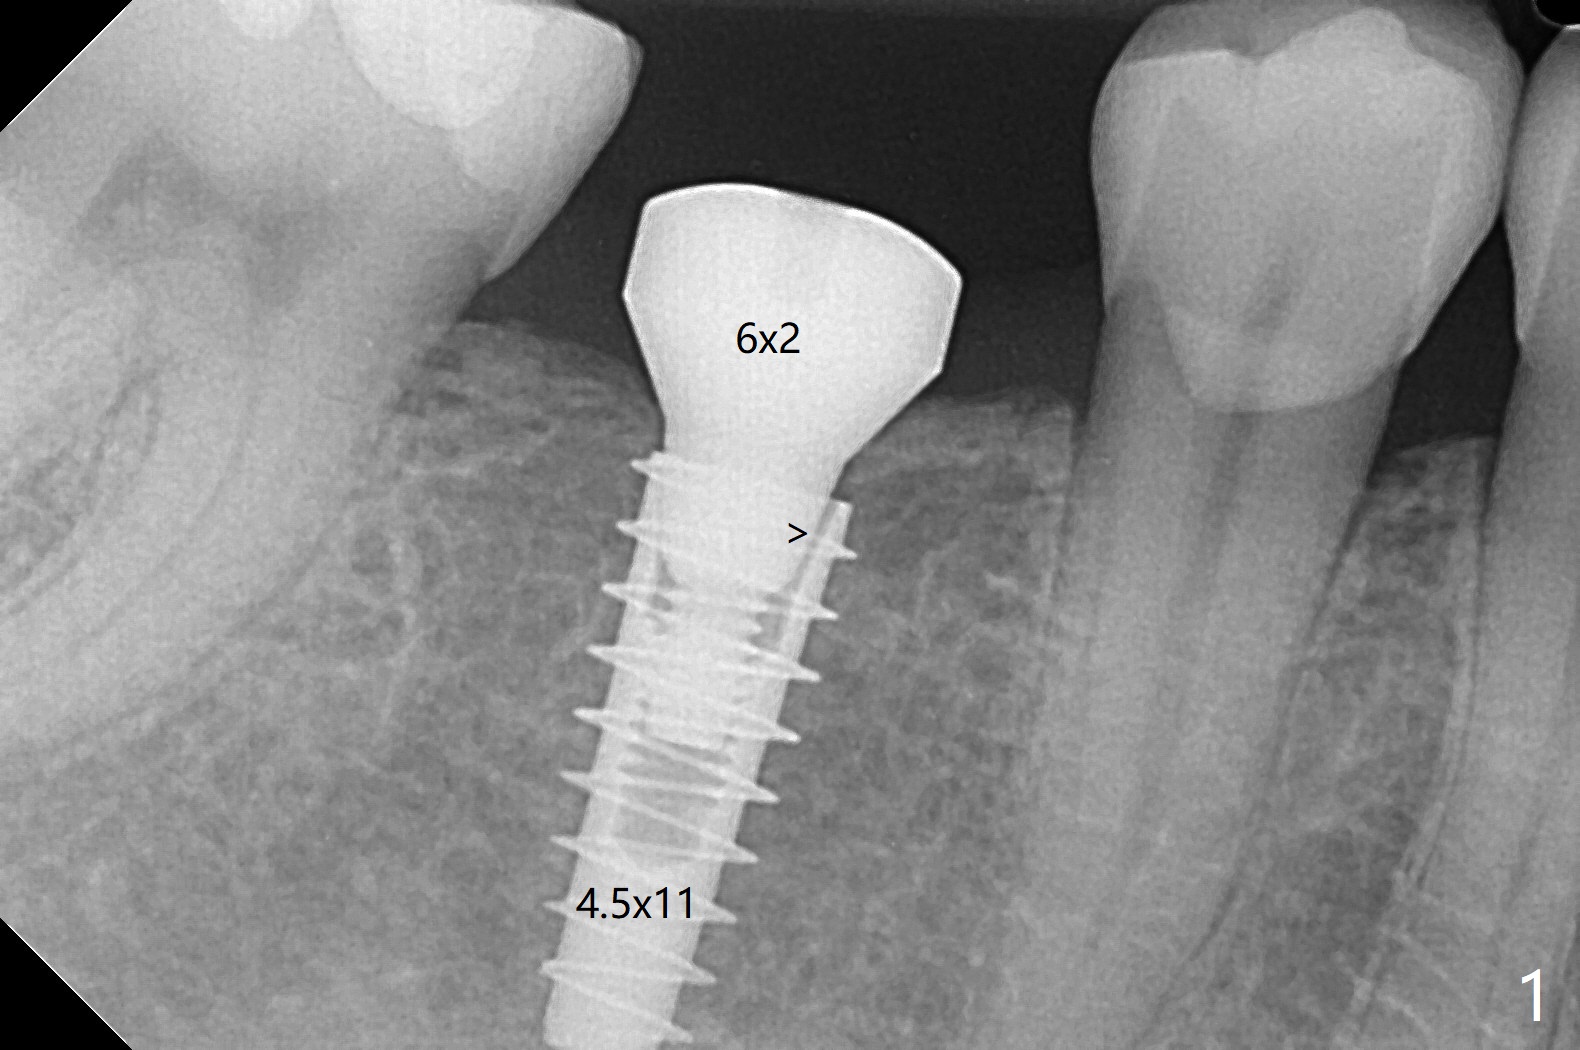

54岁男右下6缺失至少20年,牙槽嵴萎缩,使用导板顺利快速(五分钟)无痛植入4.5x11毫米植体(图一)。使用5.5毫米profile钻头后,放置6x2毫米愈合基台,后者明显没有就位(图二:箭头)。换一个基台,就位好些(图二)。再次使用同一个profile钻头后,可能去除一些近中皮质骨(图二:*),同一个基台完全就位(图三,四(红色虚线:下牙槽神经管上缘)),在愈合过程,基台不太可能脱落了。图一,二使用小sensor,而图三,四:大sensor。尽管使用小钻头(3.5毫米),扭力约20Ncm。